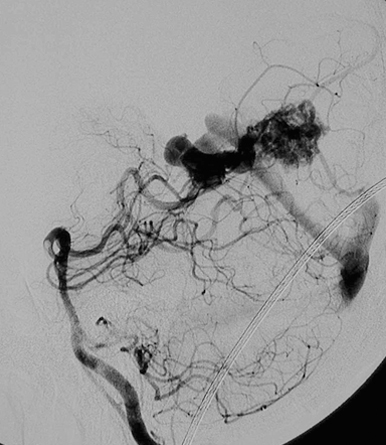

Neurosurgery10 脳動静脈奇形治療のこれまでとこれから 新到着 新NS 10】脳動静脈奇形治療のこれまでとこれから NOWの詳細情報

新到着 新NS 10】脳動静脈奇形治療のこれまでとこれから NOW。脳神経外科 専門治療 脳動静脈奇形|東京慈恵会医科大学附属柏病院。脳・脊髄動静脈奇形と頭蓋内・脊髄硬膜動静脈瘻。2017年発行の第1版です。【JMECC受講テキスト】内科救急診療指針2022【裁断済み】。脳神経領域:320列面検出器CTの最新画像がもたらす新たな展開。よろしくお願い致します。